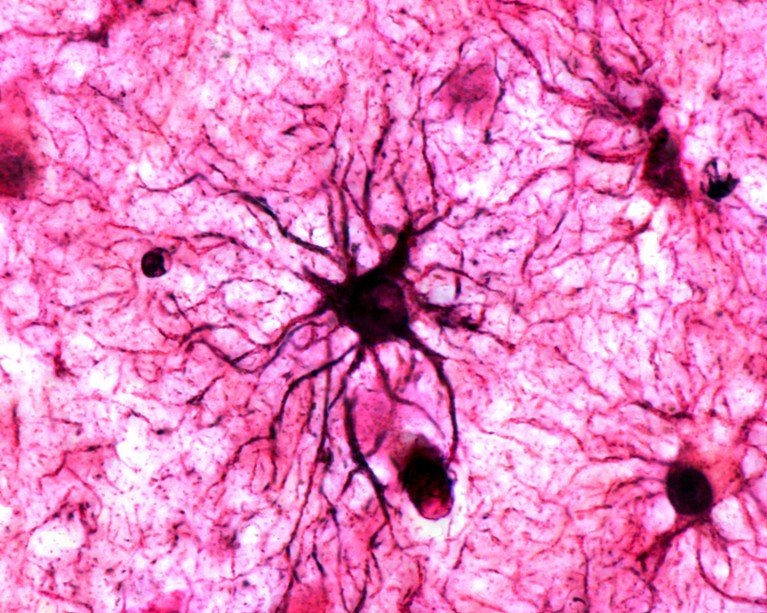

A type of brain cell called astrocytes play a crucial role in stabilizing memories in the brain.Credit: Jose Calvo/SPL

يلعب نوع من خلايا الدماغ يسمى الخلايا النجمية دورًا حاسمًا في تثبيت الذكريات في الدماغ.الائتمان: خوسيه كالفو / SPL